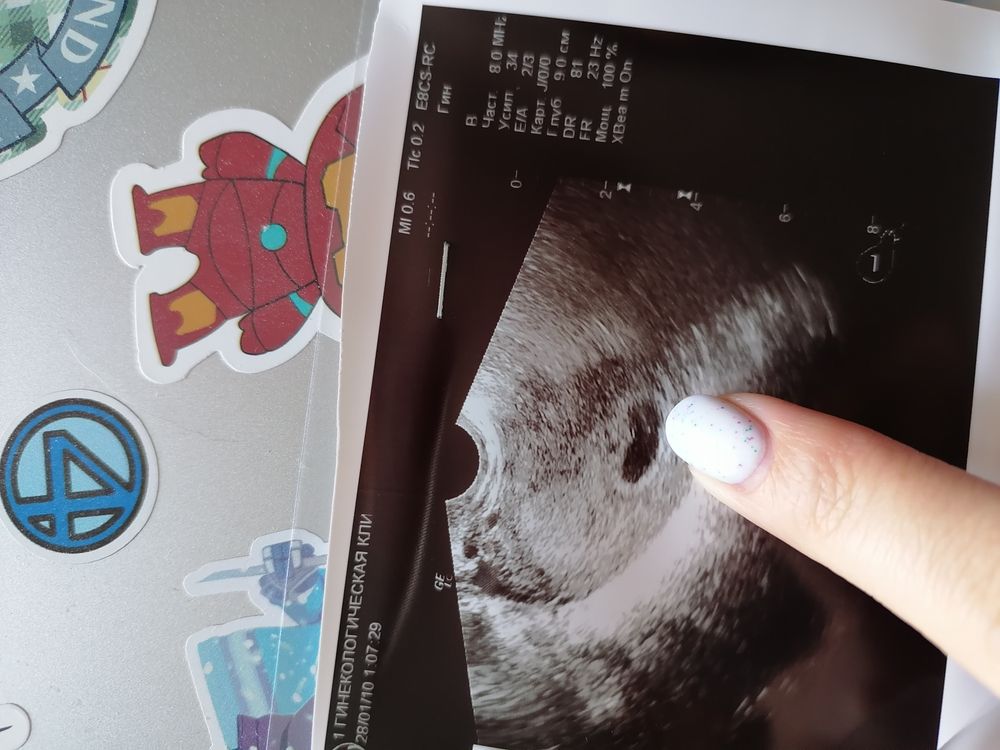

У меня на УЗИ в 7 недель пя было длинное, как сосиска и ещё и боли были адские. Пила только магний, боль прошла к 10ой неделе примерно. Сейчас вот эта сосиска рядом спит)))

Екатерина Тасова, вот даже фото нашла)) благополучно вам доходить и лёгких родов!)

Добрый день! У меня вот такое было, даже не сказали ничего про это. На первом фото без мбриончика, на втором уже с ним